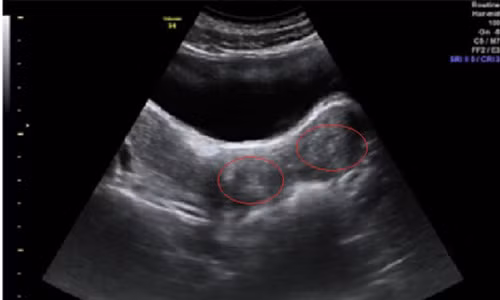

Sau khi được nhập viện, bé được thông tiểu. Kiểm tra qua đường trực tràng có khối căng to đè vào trực tràng và kết quả siêu âm thấy khối tụ máu lớn 140x60 mm, lan từ tử cung đến âm đạo, buồng trứng.

| Hình ảnh siêu âm cho thấy hai tử cung đều dị dạng. (Ảnh do bệnh viện cung cấp) |

Sau tiến hành phẫu thuật, kiểm tra siêu âm lại các bác sĩ kết luận bé gái bị dị dạng hai tử cung, hai âm đạo nhưng có một âm đạo không thông với màng trinh dẫn đến việc ứ máu khi đến tháng, gây đau cũng như chèn ép gây bí tiểu và táo bón. Bên cạnh là dị dạng tiết niệu với một quả thận duy nhất.